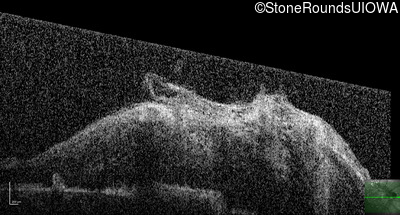

This 9 year old male was noted to have some crossing of his eyes at 2 months of age and the eye exam which followed identified a retinal lesion in the right eye. When he was six years old an epiretinal membrane was noted in his left eye. Two years later it was decided that it was a thin hamartoma in that eye as well. He underwent neuroimaging at age 7 which identified bilateral acoustic neuromas.

| Age at visit: 8 years |

| Age at visit: 10 years |

| Age at visit: 11 years |

| Age at visit: 14 years |